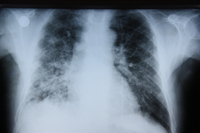

Assessment of persistent pulmonary infiltrate

Chest x-ray of a patient with amiodarone pulmonary toxicity

From the collection of Athanasia Pataka, MD